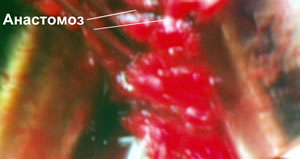

и приступил к наложения анастомоза между отсеченной уретрой

и шейкой мочевого пузыря (схема).

Анастомоз наложен (схема).